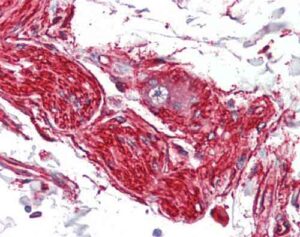

Un passo in avanti verso una migliore comprensione dell'endometriosi. Un nuovo studio pubblicato sull'American Journal of Pathology ha scoperto che...